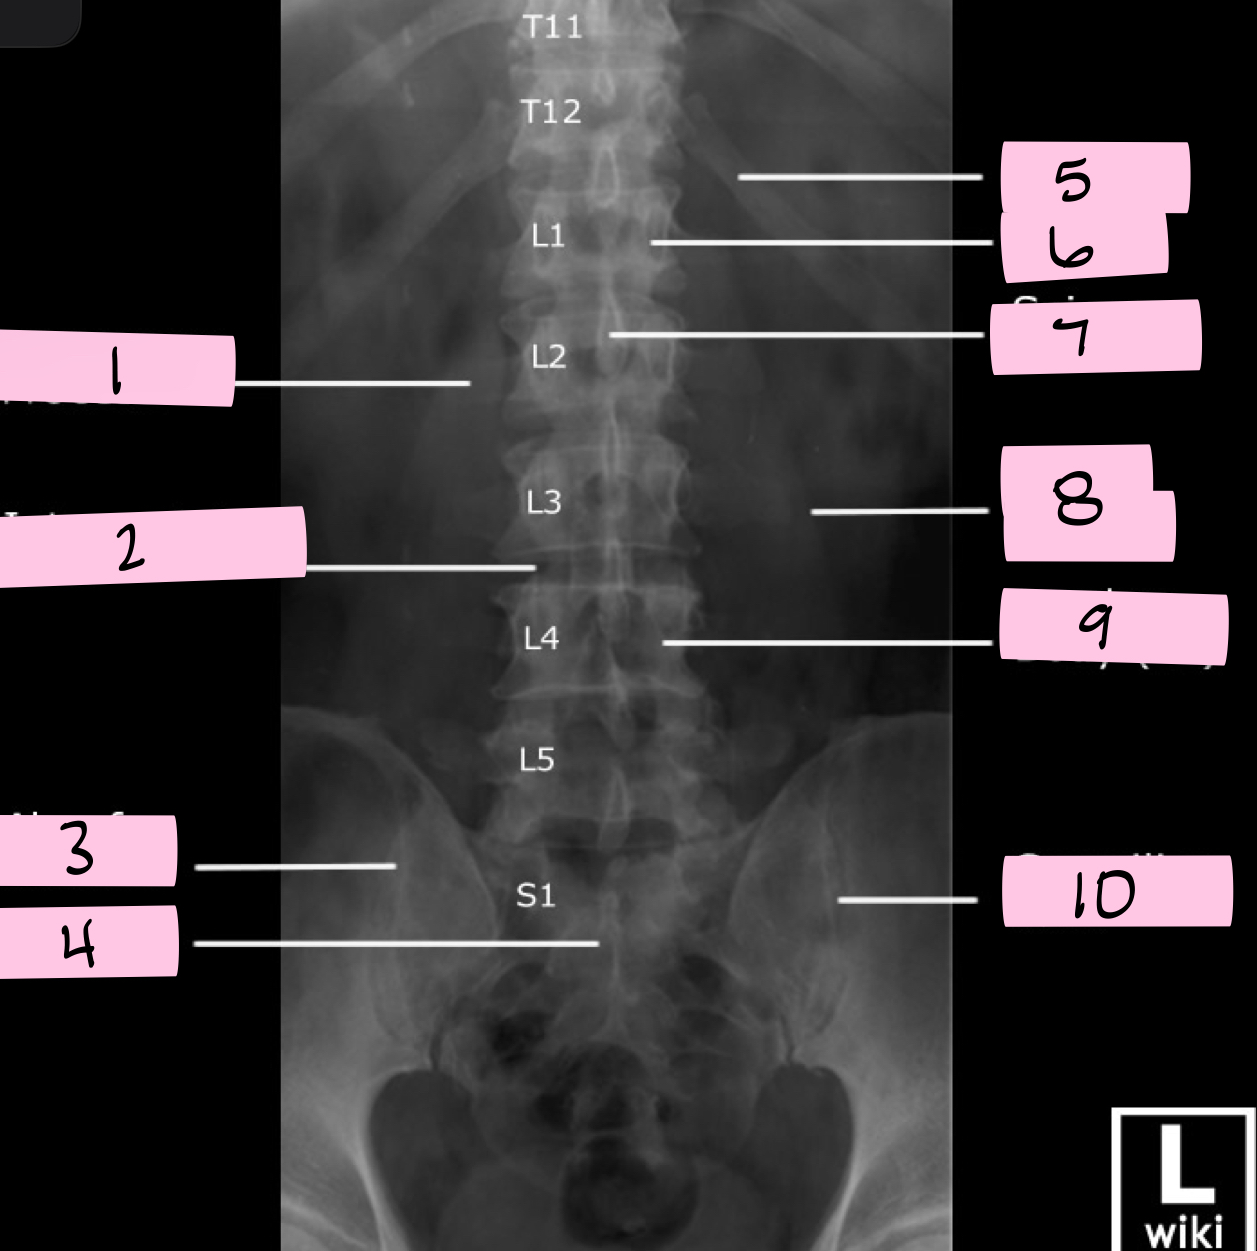

What is 1 pointing to?

Transverse process

What is 2 pointing to?

Intervertebral disk

What is 3 pointing to?

Ala of sacrum

What is 4 pointing to?

Sacrum

What is 5 pointing to?

12th Rib

What is 6 pointing to?

Pedicle

What is 7 pointing to?

Spinous process

What is 8 pointing to?

Psoas muscle

What is 9 pointing to?

Lumbar body (L4)

What is 10 pointing to?

Sacroiliac joint